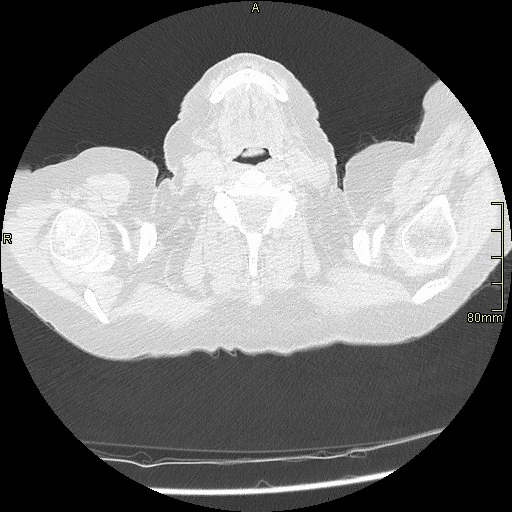

HRCT - Axial Prone Inspiration (Soft Tissue Window)

HRCT - Axial Supine Inspiration (Soft Tissue Window)

HRCT - Axial Supine Expiration (Soft Tissue Window)